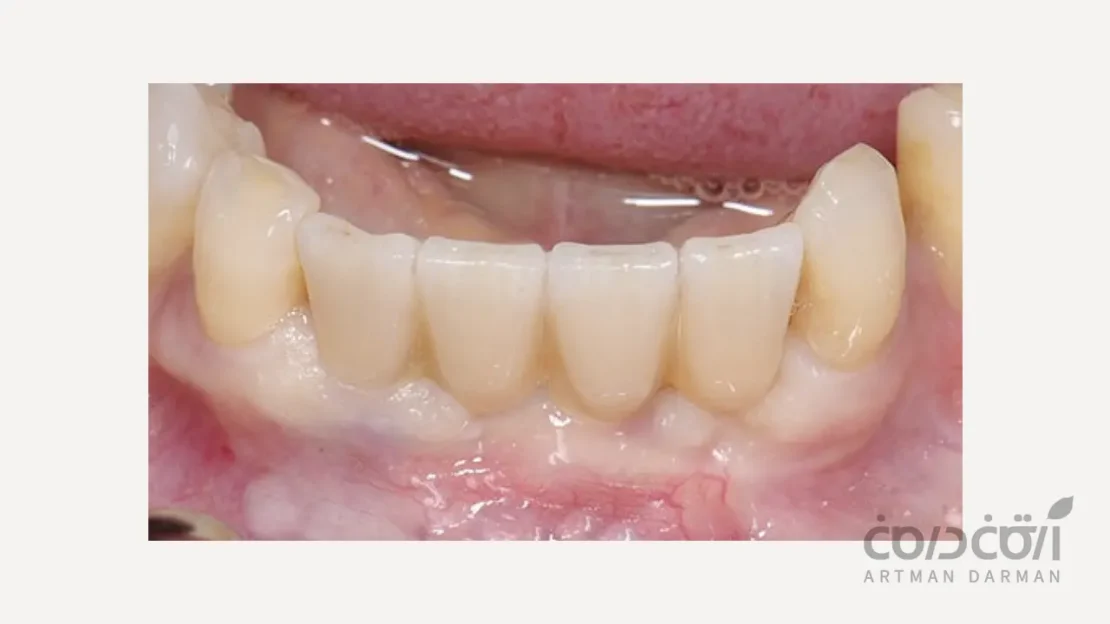

بهترین نتایج زیبایی شناختی

این روش به دندانپزشک و تکنسین لابراتوار اجازه می دهد تا فرم طبیعی لثه بین دندانی (پاپیلا) را به بهترین شکل ممکن بازسازی کرده و یک نتیجه کاملاً طبیعی خلق کنند.

ماندگاری و پیش آگهی عالی

از آنجایی که تمام اصول بیومکانیک و بیولوژیک رعایت شده، این روش بالاترین میزان موفقیت و ماندگاری را در بلندمدت دارد. و طبیعی است که بهترین انتخاب برای جایگزینی دو دندان با ایمپلنت محسوب می شود.

استاندارد طلایی و بهترین راه حل برای جایگزینی دو دندان با ایمپلنت، استفاده از دو ایمپلنت مستقل با دو روکش مجزا است. این روش، با تقلید از ساختار و عملکرد طبیعت، بالاترین میزان موفقیت، دوام، بهداشت پذیری و زیبایی را برای شما به ارمغان می آورد.